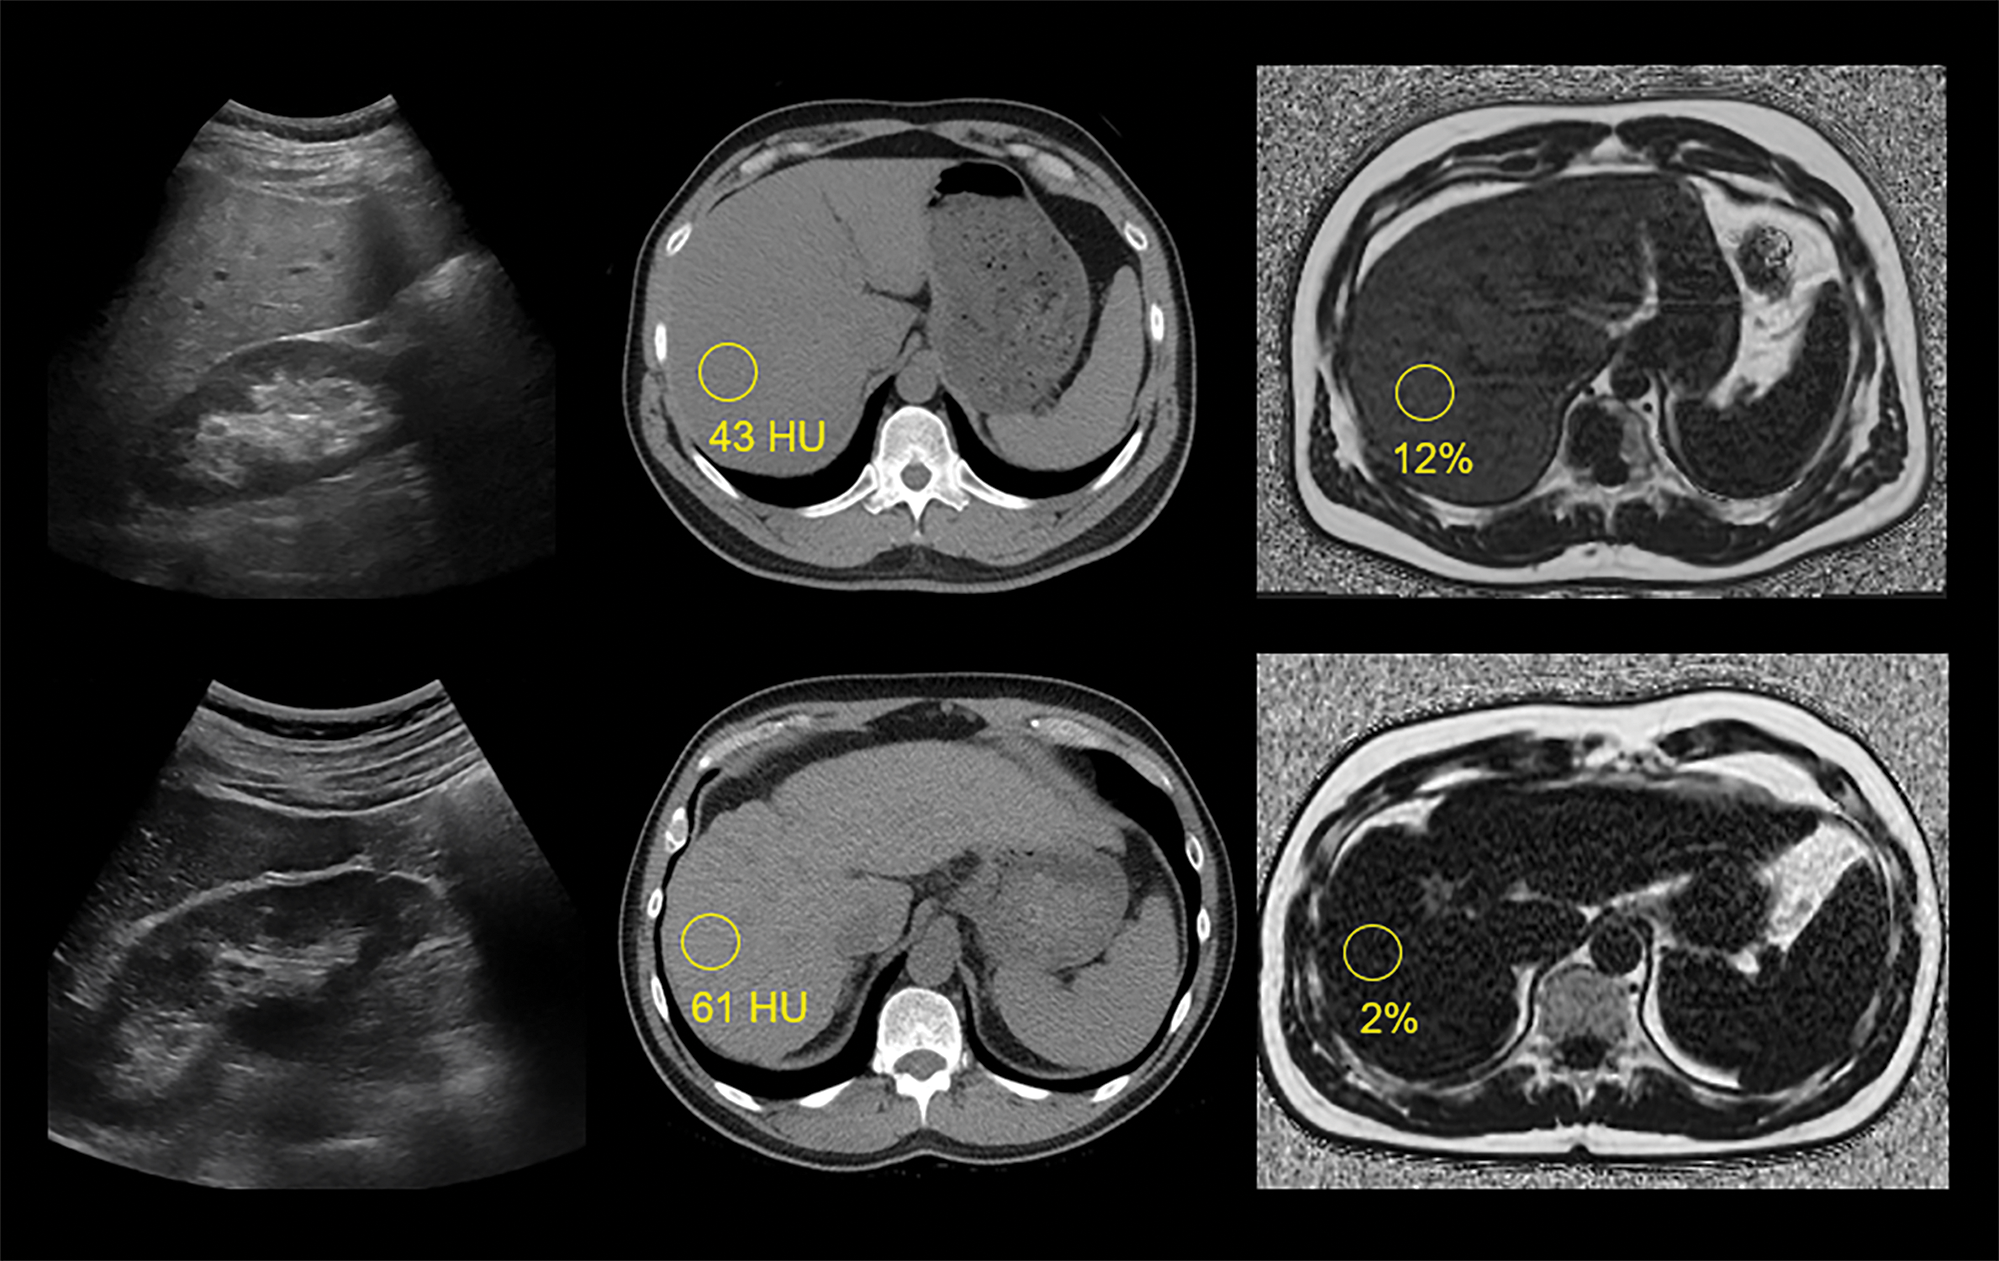

Examples of steatotic and fibrotic livers at US, non‑contrast CT, and MR‑PDFF.

Top row images are from a 44‑year‑old man with mild‑moderate hepatic steatosis, including a conventional US image (left) showing subjectively increased parenchymal echogenicity, particularly compared to adjacent renal parenchyma, a non‑contrast CT image (middle) with liver measuring 43 HU, and an MR‑PDFF map (right) showing 12% fat fraction.

Bottom row images are from a 58‑year‑old man with chronic liver disease and advanced fibrosis but without steatosis, including a conventional US image (left) showing normal parenchymal echogenicity, a non‑contrast CT image (middle) with liver measuring 61 HU, and an MR‑PDFF map (right) showing 2% fat fraction. Note CT and MR findings of advanced fibrosis or cirrhosis, including nodular liver contour and segmental redistribution.